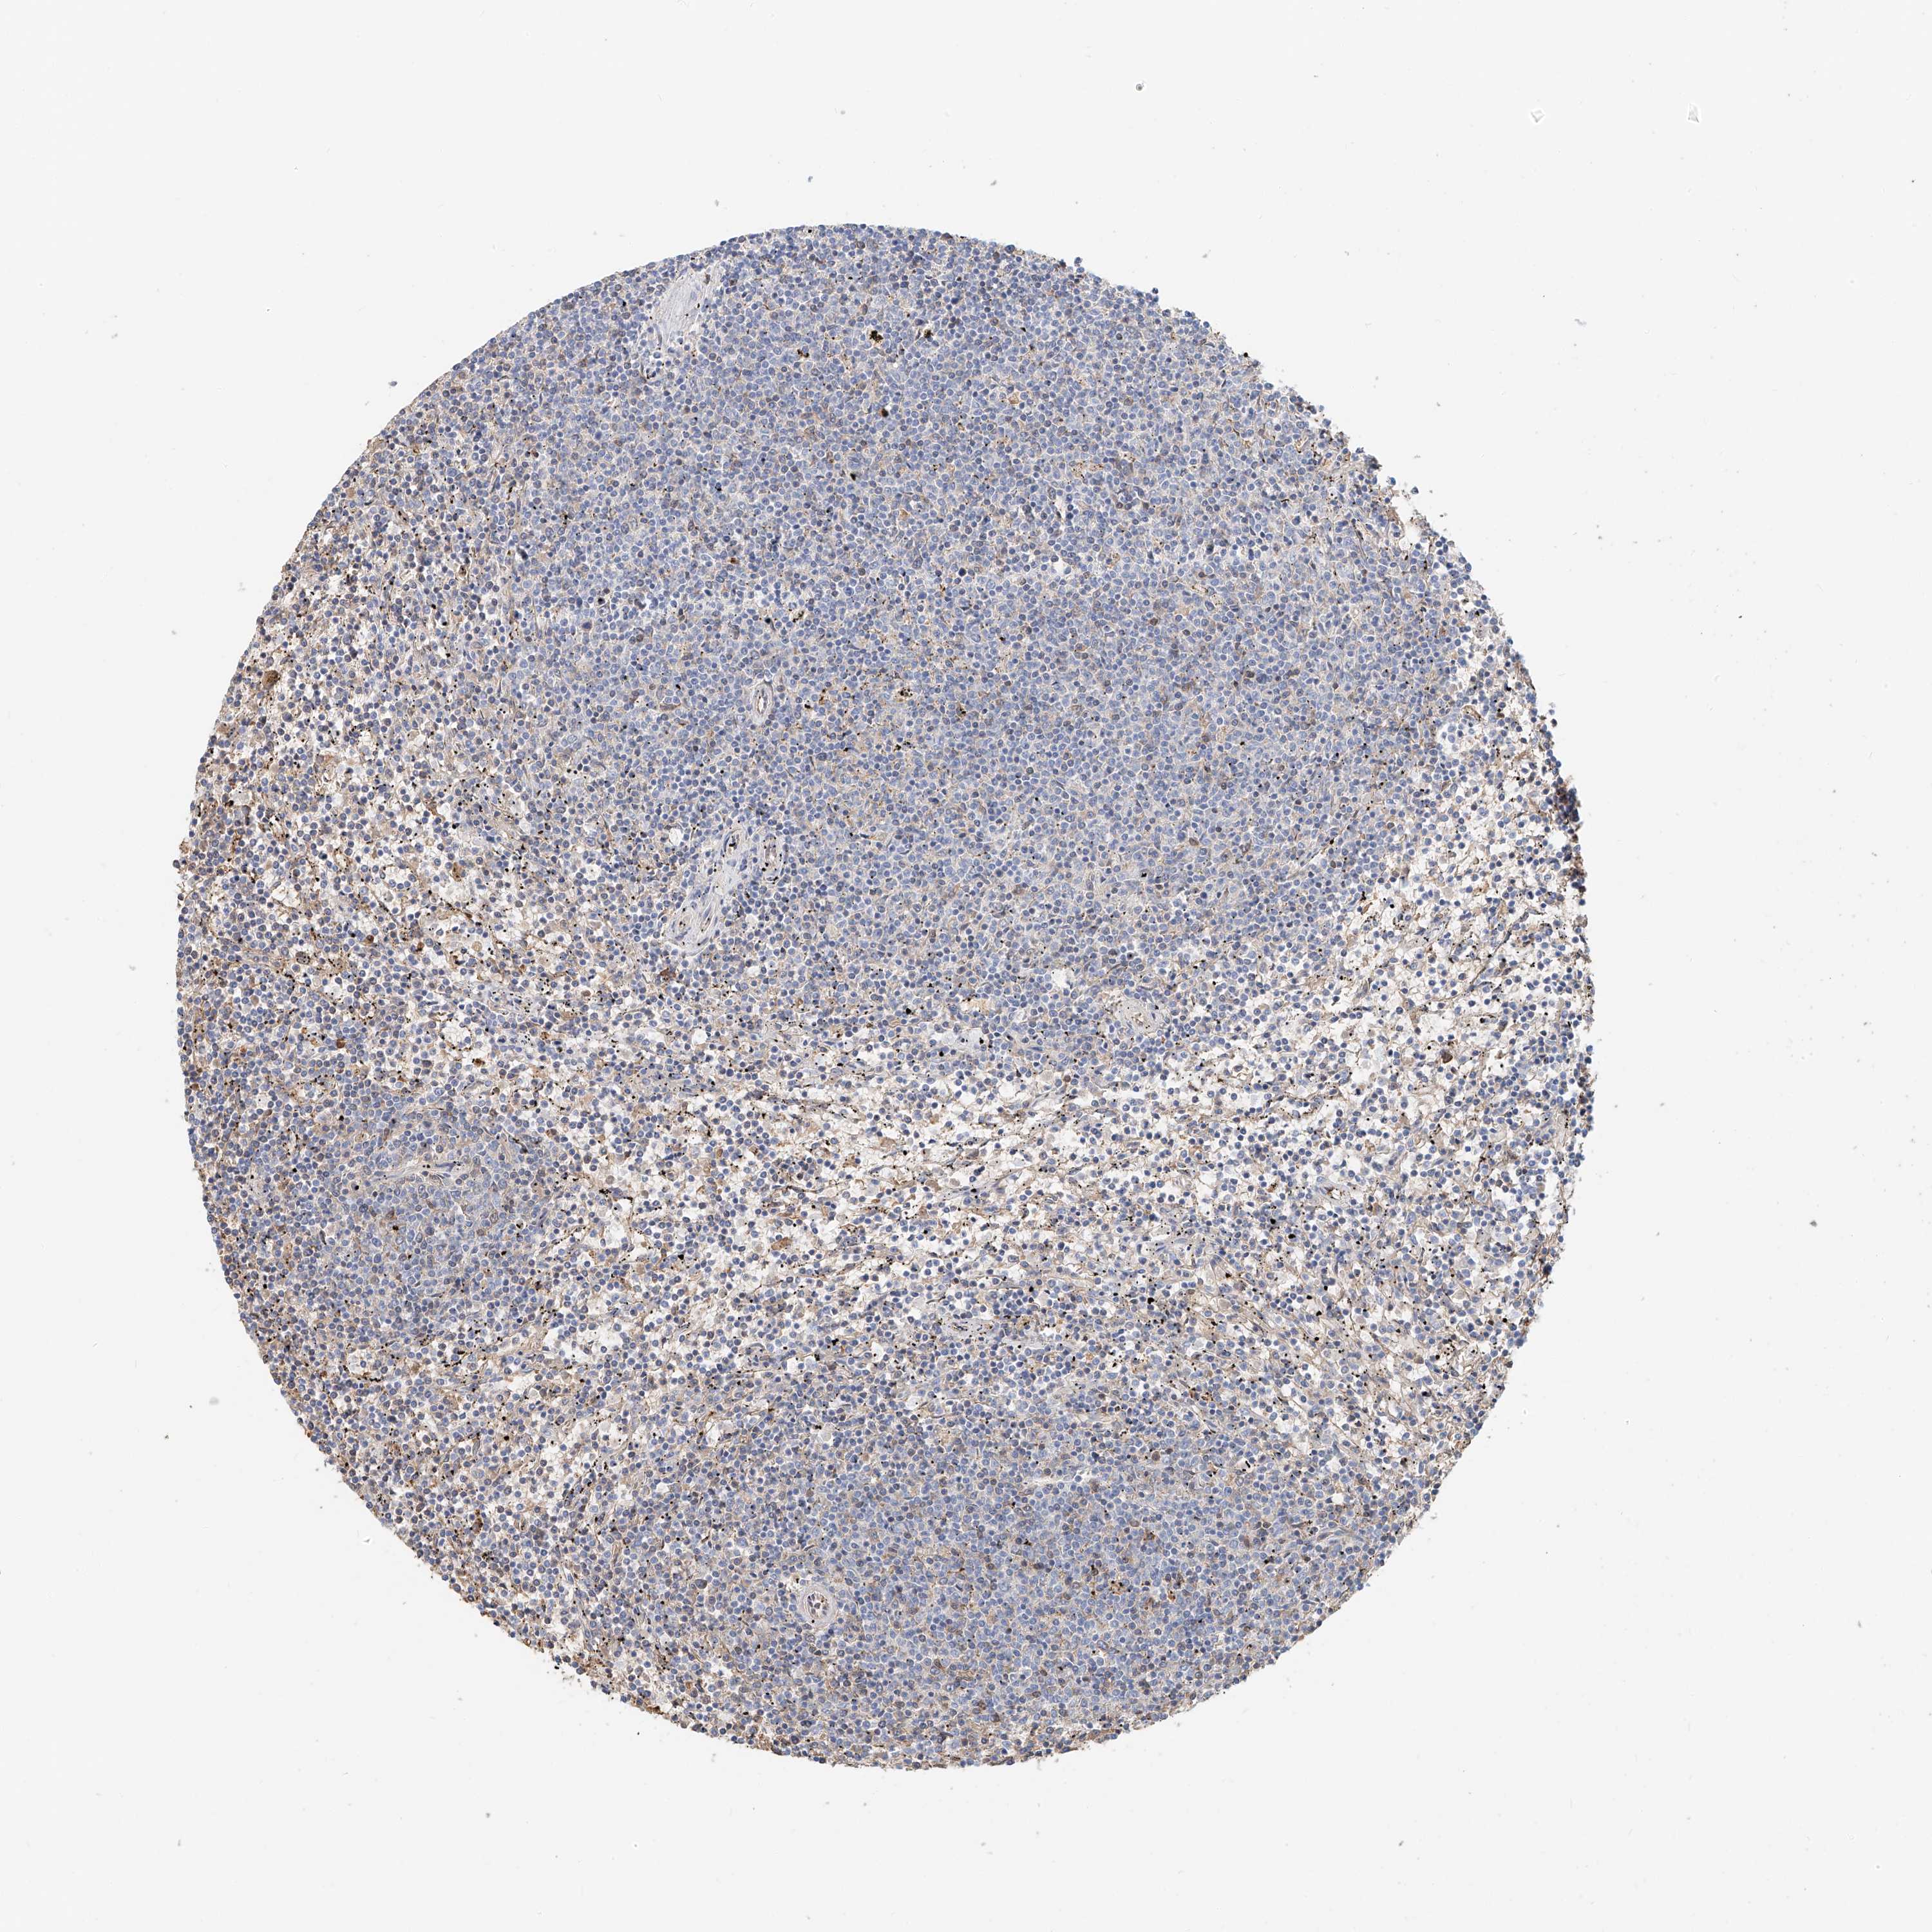

CANCER LYMPHOMA Show tissue menu

LYMPHOMA - Protein expressioni

A mouse-over function shows sample information and annotation data. Click on an image to view it in a full screen mode. Samples can be filtered based on level of antibody staining by selecting one or several of the following categories: high, medium, low and not detected. The assay and annotation is described here.

Each image is clickable and will lead to virtual microscopy that enables deeper exploration of all samples and also displays staining intensity scores, fraction scores and subcellular localization as well as patient and tissue information for each sample.

Antibody HPA030606

Staining

High

Medium

Low

Not detected

Intensity

Strong

Moderate

Weak

Negative

Quantity

>75%

75%-25%

<25%

None

Location

Nuclear

Cytoplasmic/membranous

Cytoplasmic/membranous,nuclear

Hodgkin's disease, NOS

Malignant lymphoma, non-Hodgkin's type, High grade

Malignant lymphoma, non-Hodgkin's type, Low grade